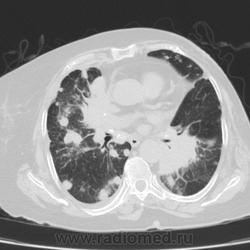

Метастатическое поражение легких.

Пожилая женщина, 76 лет находится на стац.лечении, провели СКТ дообследование.  Сопут- сr левой молочной железы. Такие множественные

поражения  в легких встречаются не часто.

Раннее несколько лет назад оперирована по поводу рака левой молочной железы.